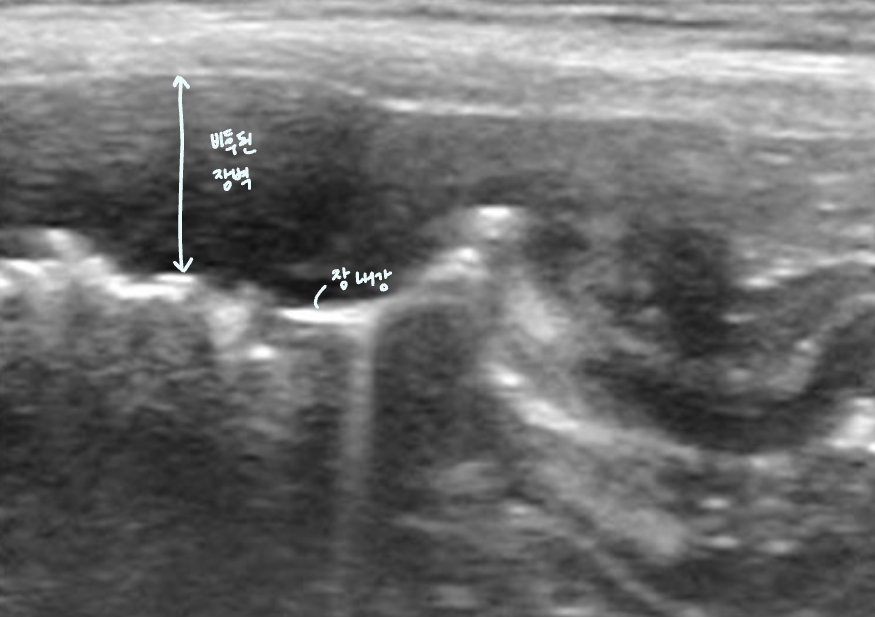

| Stacking sign |

| ์ฅ์ด ์ปค์ ธ์ ์ข์ ๊ณต๊ฐ ์์ ์ฐจ๊ณก์ฐจ๊ณก ์์ด๋ฉฐ ๋ณด์ด๋ sign. |